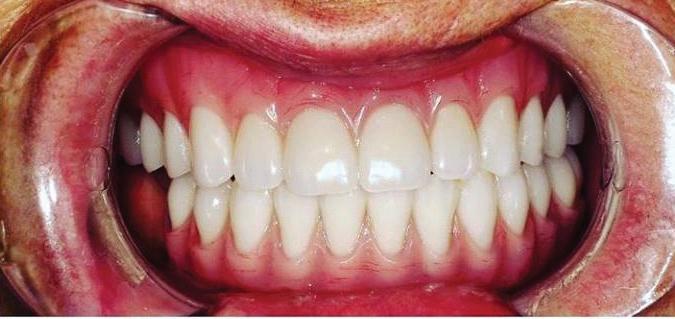

By Ali Ghatri, DDS Let’s Smile Dental

Dental implant procedures are complex and require the expertise of multiple dental professionals, each contributing their unique skills to achieve a successful and long-lasting result.

The general dentist typically serves as the primary point of contact. They initiate the diagnostic process, evaluate overall oral health, and determine whether the patient is a candidate for implants. The general dentist also handles initial care such as extractions, treatment of decay, or periodontal therapy. Once the need for collaboration is identified, the dentist coordinates referrals to the appropriate specialists.

An orthodontist may be involved early in the planning process, particularly if teeth have shifted into the space of a missing tooth or if bite alignment needs correction. Strategic tooth movement is often essential before implant placement, especially since implants, once placed, are immovable. Orthodontists use tools like braces or clear aligners to create optimal spacing and alignment, not just for aesthetics, but also to ensure the long-term success of the implant.

The oral surgeon is responsible for the surgical phase of treatment. This includes placing the titanium implant post into the jawbone with precision, sometimes performing additional procedures such as bone grafting or sinus lifts when necessary. Their goal is to ensure a solid foundation for the future res-

toration while minimizing surgical risk and promoting proper healing. In some cases, the oral surgeon may also consult with a periodontist to manage the health and shape of the gum tissue surrounding the implant. This is especially important in patients with a history of gum disease or when aesthetics are a priority in the smile zone.

Once the foundation is secure, the general dentist may work with a prosthodontist to design and place the final restoration—typically a crown, bridge, or denture. Prosthodontists specialize in restoring function and appearance with highprecision prosthetic teeth.

While collaboration between providers was introduced in the

first article, this second part highlights the distinct roles each professional plays during the process. The timing and sequence of care matter, and it’s often the general dentist who coordinates this multidisciplinary effort to ensure that every stage of treatment is integrated, efficient, and tailored to the patient’s needs.